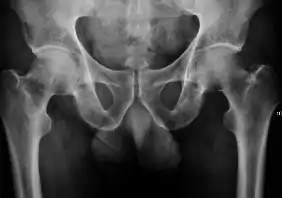

Projectional radiography ("X-ray") is the first imaging technique of choice in hip pain, not only in older people with suspected osteoarthritis but also in young people without any such suspicion. In this case plain radiography allows categorization as normal hip or dysplastic hip, or with impingement signs, pincer, cam, or a combination of both.[1]

Projectional radiography ("X-ray") is currently useful not only in older people in whom osteoarthritis of the hip is suspected but also in younger people without osteoarthritis, who are being evaluated for femoroacetabular impingement (FAI) or hip dysplasia.[1]

Plain radiography allows us to categorize the hip as normal or dysplastic or with impingement signs (pincer, cam, or a combination of both). Besides these, pathologic processes like osteoarthritis, inflammatory diseases, infection, or tumors can also be identified (Figure 1).[1]